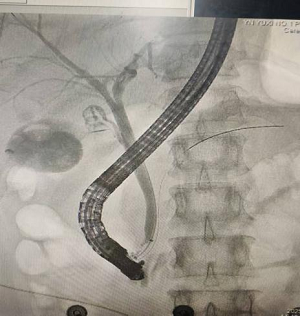

9月19日,肝胆胰-甲状腺-血管外科医生为患者行“ERCP(经内镜逆行胰胆管造影)+EST(内镜下乳头括约肌切开术)+EPBD(内镜下乳头球囊扩张术)+胆管取石术+ENBD(内镜下鼻胆管引流术)+ERPD(内镜下胰管引流术)”手术。在内镜治疗下为患者取出胆总管结石,术后留置鼻胆管引流,两天后,患者拔除鼻胆管,一周后患者康复出院。

术中影像